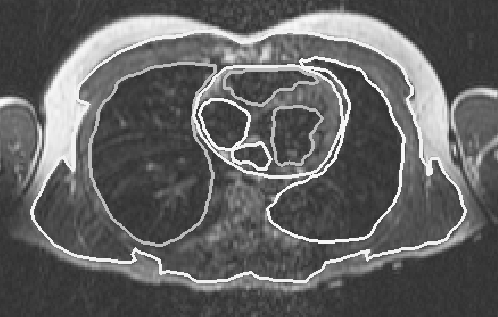

The model in this study was constructed primarily from 115 transverse MRIs of a healthy adult male. The images were taken every 5 mm beginning just below the waist and ending at the bottom of the neck. In each two-dimensional image, the regions of interest were segmented into contours. Figure 1 shows the segmentation contours of several major regions in one of the images that included the heart. The segmentation was accomplished with a segmentation program that allowed the user to view the MRI to manually select boundary points with a mouse [22, 23]. The points for each contour were used to create a spline that was then resampled to establish regular spacing and saved as a set of x,y coordinates describing the contour at a particular z level. In this way, regions of particular tissue types (for example, subcutaneous fat) as well as anatomical structures (such as the right atrium) were specified. The larger tissue regions of the model included the subcutaneous fat, the skeletal muscle, the lungs and the bones of the torso. In the vicinity of the heart, more detailed anatomical structures were specified. These structures included both atria and ventricles, three epicardial fat pads and the following components of the great vessels: the superior and inferior vena cava, the pulmonary arteries and veins, the ascending and descending aorta, the azygous vein, and the left and right subclavian veins. All of the contours in the different z planes for a particular structure, such as a lung, were then connected into triangles to construct a closed surface.

Figure 1: Magnetic resonance image of the thorax with superposed segmentation boundaries. The projection of the image is caudal-cranial and tissue boundaries include subcutaneous fat, lungs, and epicardial and endocardial borders of the heart.